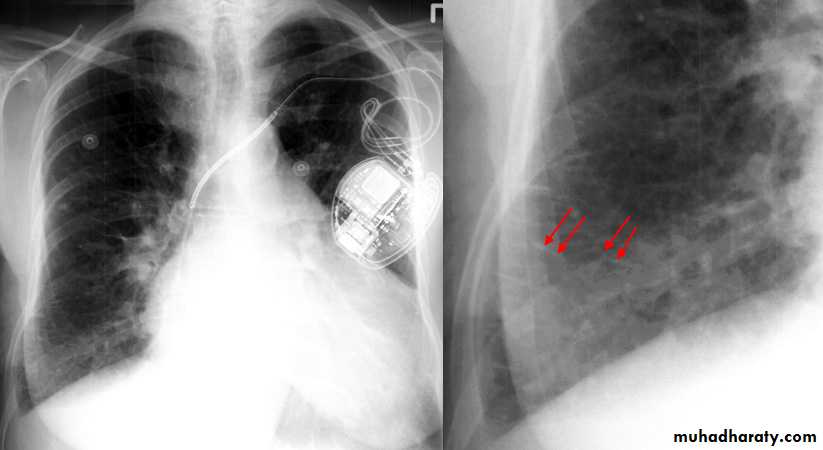

Pleural Effusion on Chest Radiographs.

Posteroanterior (A) and lateral (B) chest radiographs demonstrate the typical meniscoid appearance (arrows) in a patient with a left pleural effusionHydropneumothorax.